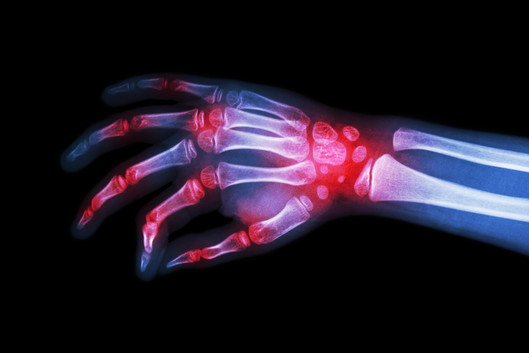

Ein weiterer Schwerpunkt der Klinik besteht in der Durchführung sämtlicher Wahleingriffe bei Erkrankungen an der Hand, wie beispielsweise arthrotische Veränderungen an den Gelenken, Nervenkompressionssyndrome, Sehnenveränderungen, Dupuytren'sche Kontrakturen, aber auch tumoröse Veränderungen oder Fehlbildungen an der Hand, einschließlich sämtlicher Revisionseingriffe.